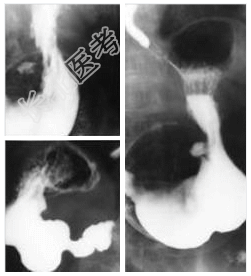

- [材料题] 女性,30岁,上腹部疼痛、返酸1年余,近一周加重。疼痛反复,秋冬季明显,餐后疼痛明显,下次进餐前缓解。查体:剑突下左侧轻压痛,腹部平软。行上消化道钡餐透视及照片检查。

- 简答题1、患者的诊断及依据是什么?

- 简答题2、鉴别诊断有哪些?